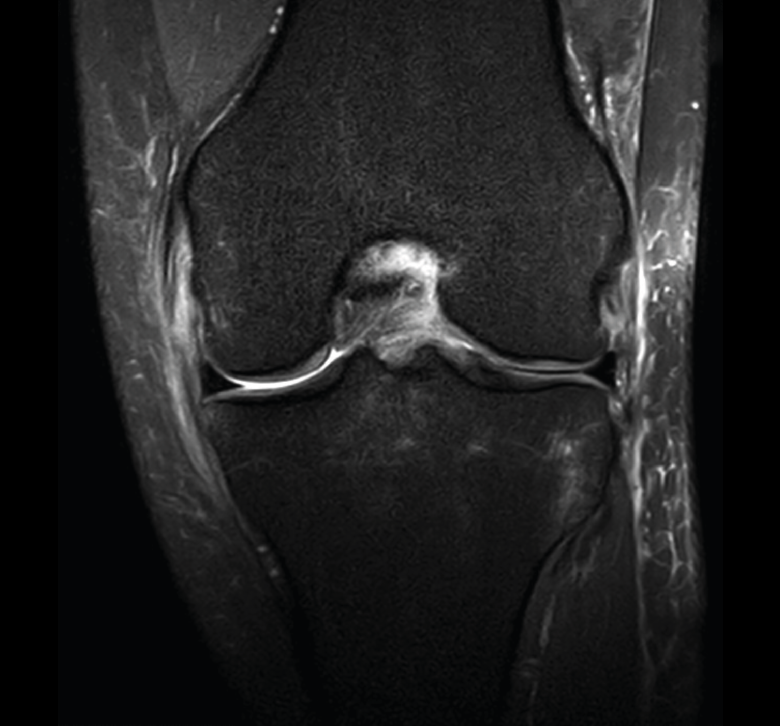

La RM es la técnica de elección en el diagnóstico de la patología meniscal(17)(Figuras 30, 31, 32, 33, 34 y 35).

Figura 32. Corte de secuencia coronal T2 Fat-Sat de resonancia magnética de rodilla: rotura de menisco interno horizontal.

Figura 35. Corte de secuencia coronal y sagital de resonancia magnética de rodilla: rotura en asa de cubo del menisco interno con fragmento desplazado al intercóndilo.

1.2. Ligamentos